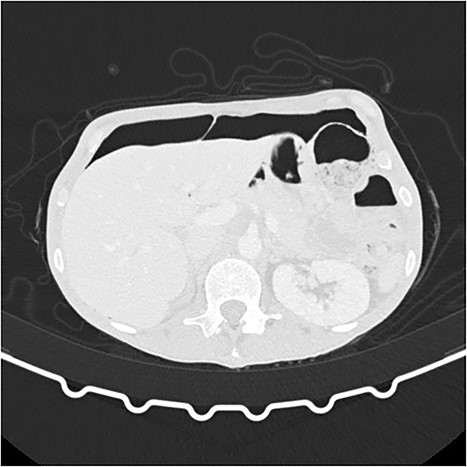

A 63-year-old woman underwent an elective hysterectomy and bilateral adnexectomy due to a large right adnexal mass (290 × 190 mm). On the sixth postoperative day, she developed nausea and vomiting, along with abdominal distension and generalized abdominal pain, without peritoneal signs or guarding. An abdominal X-ray was requested, which showed pneumoperitoneum and multiple air-fluid levels in the small intestine. Blood tests were unremarkable. An abdominal and pelvic computed tomography (CT) scan was also performed, revealing “pneumoperitoneum in a quantity above what would be expected given the postoperative timeline, with no image suggestive of hollow viscus or vaginal cuff dehiscence.” (Figs 1 and 2). Based on the clinical findings, a conservative approach was chosen. A nasogastric tube was placed, and the patient was put on a nil-by-mouth diet. Two days later, she began an oral diet and resumed intestinal transit, maintaining a favorable clinical course for the remainder of her hospital stay.